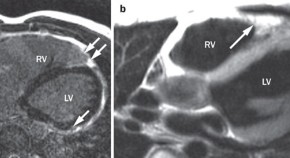

The morphology, structure and position of the right ventricle differ substantially from those of the left ventricle and have posed difficulties in the assessment of right ventricular function. Imaging techniques, notably echocardiography and MRI, have enabled a better understanding of right ventricular performance. Mertens and Friedberg discuss the advantages and disadvantages of established and new methods of right ventricular imaging and their potential in the clinical setting.